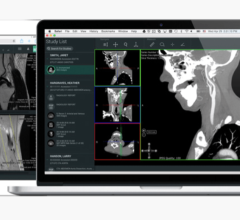

Based in Edinburgh, Scotland, Barco’s Advanced Visualization (AVIS) group is specialized in 3D clinical software solutions, marketed worldwide under the product names ‘Voxar 3D’ and ‘Voxar 3D Enterprise.’ As part of the agreement, TMVS will become the new owner of all AVIS assets, including its full product portfolio. TMVS will help support the development of 3D volume rendering and advanced visualization capabilities for all Toshiba modalities.